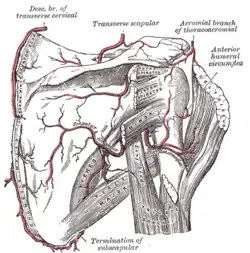

Diagrama de la articulación del hombro, vista frontal.

Diagrama de la articulación del hombro, vista frontal. -